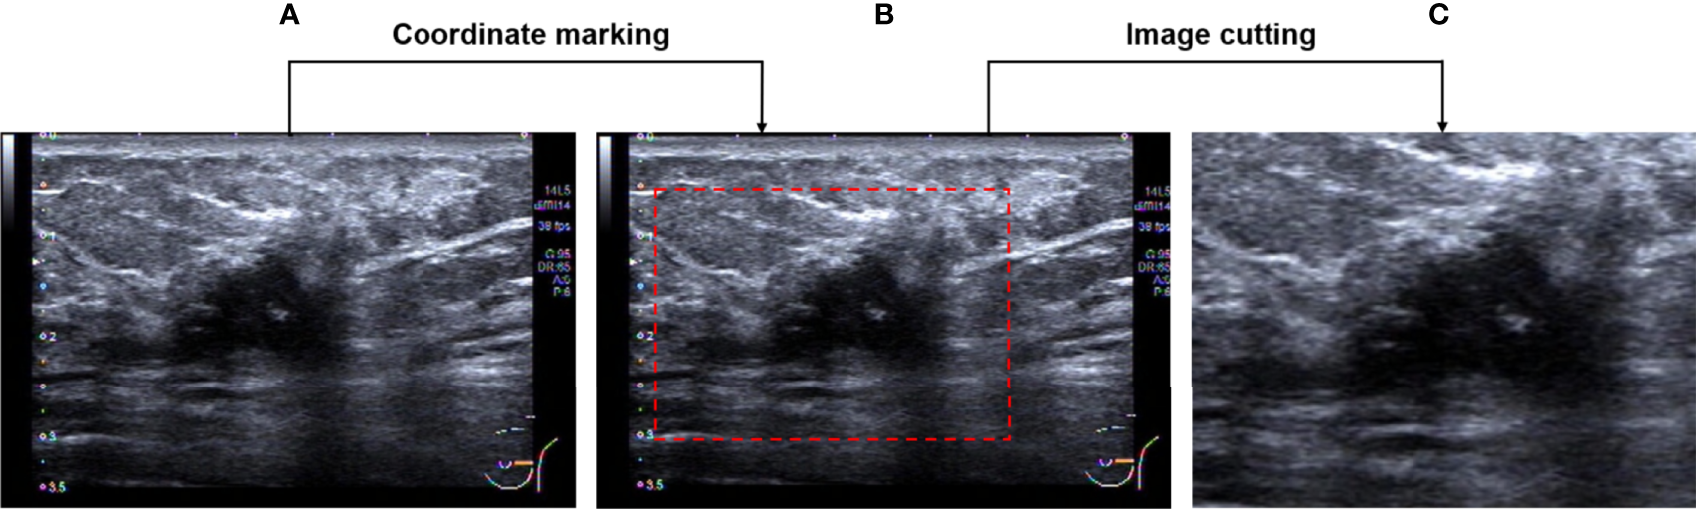

Firstly, the region of interest (ROI) which includes the entire tumor area, as well as the minimum peritumoral tissue was manually cropped in breast US images which were completed by a senior radiologist with 12 years of experience. An example of the ROI of breast US images is shown in Figure 2. After that, a total of 800 ROI images were obtained and then split into training and testing groups at the ratio of 75% to 25%.

Figure 2

Image pre-processing. (A) An original breast US image. (B) Image after coordinate marking. (C) The selected effective image area.